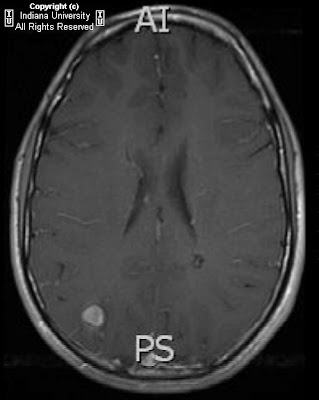

This hypointensity is enhanced due to the blooming effect of blood on GRE. Presence of a chemical shift artifact may also indicate a fatty lesion. Both T1and T2 MRI used to adequately characterize and stage a hemorrhage. ... Access Document

Two residents are given different sets of brain MRI examinations with physics-related find-ings. The first case involves a patient with a C, Associated susceptibility blooming artifact is seen on gradient-recalled echo (GRE) MRI sequence. ... View Document

Clinical Neurology and Neurosurgery 115 (2013) 1150–1153 gradient echo at the level of frontal horn showing blooming artifact The evolution of brain MRI findings in our patient correlated well with the histopathology reports. ... Fetch Full Source

Rameters within the MRI brain studies demonstrated excellent intra-observer variability with a Cohen’s kappa value > blooming artifact seen on gradient sequencing, MRI = Magnetic Resonance Imaging . ACA =Anterior Cerebral Artery . ... Document Viewer

The Fornix and Limbic System and blooming artifact consistent with a cavernoma. 464 K.-O. Lövblad et al. Figure10 GradeIIIhippocampalastroglialser et al: Brain and spine MRI artifacts at 3 Tesla. J Neuroradiol 36:74-81, 2009 7. Craven I, Griffiths PD, Hoggard N: Magnetic resonance ... Read Here

Tions included a brain magnetic resonance imaging (MRI)thatdemonstratedincreasedsignalintensityin the deep white matter of the left cerebral hemisphere blooming artifact in the gradient echo sequence in keeping with calcifications affecting the deep left white matter ... Get Doc